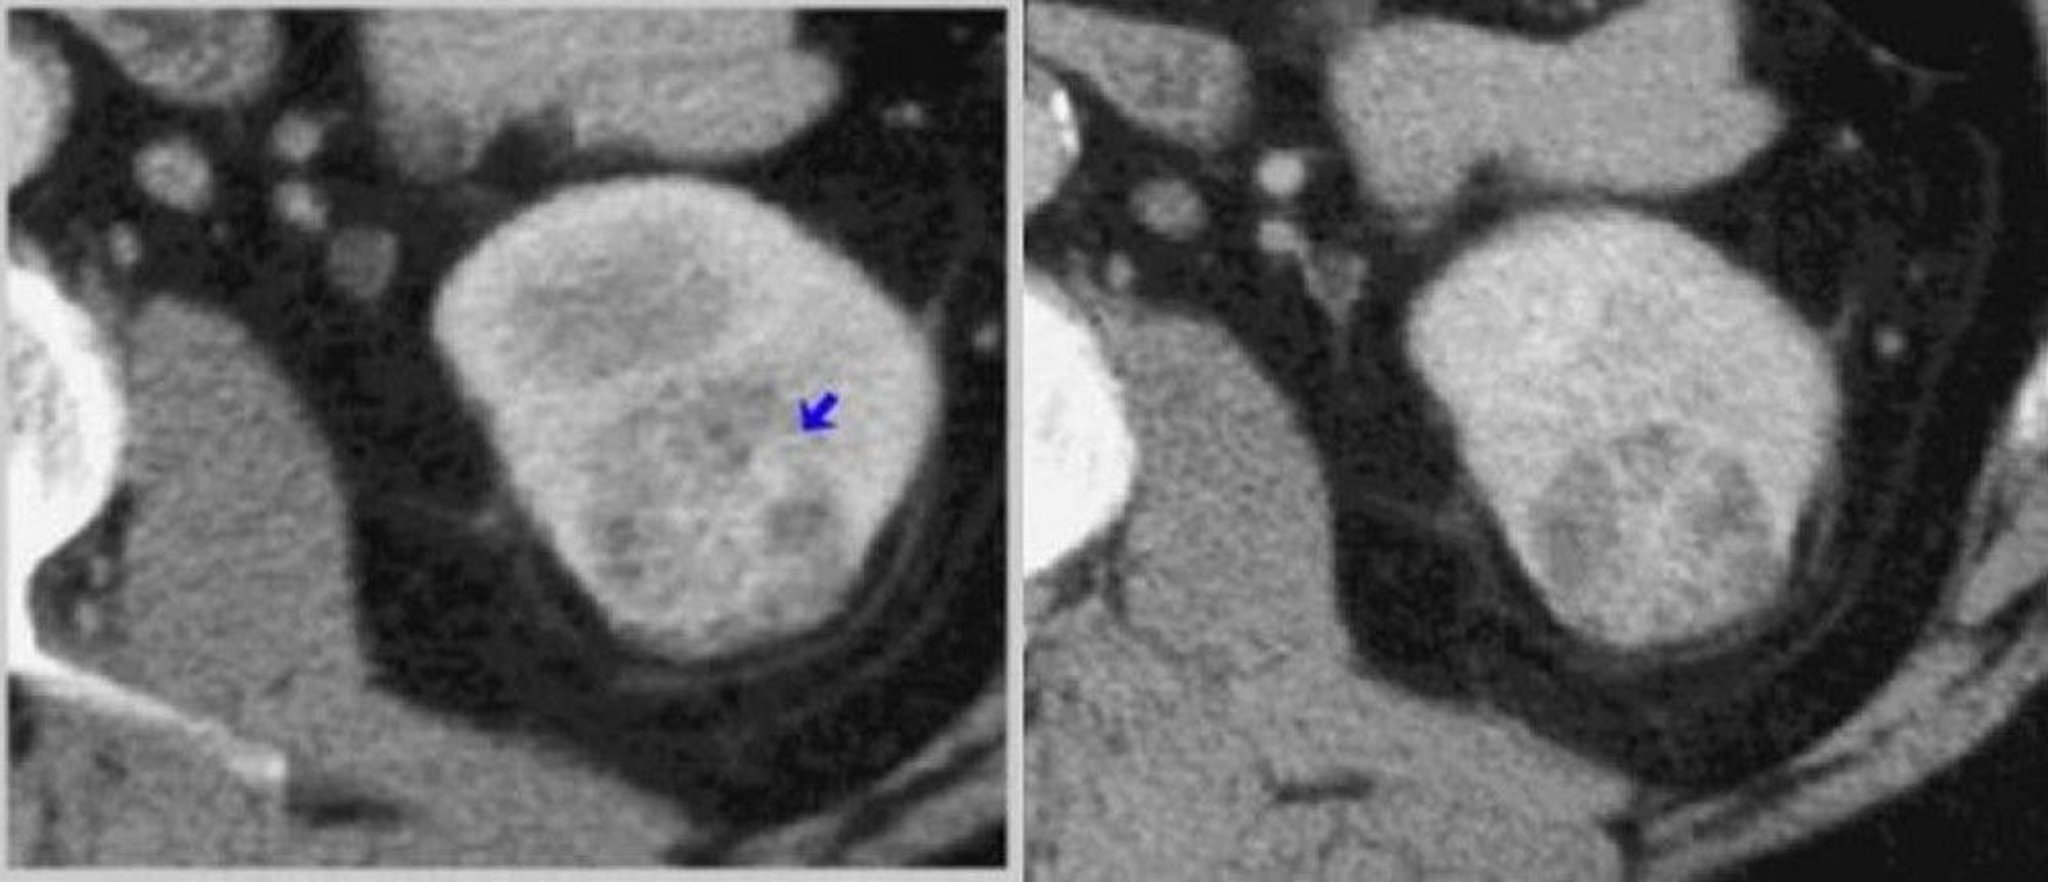

腎臓の造影CT(皮髄相および腎実質相)

左の画像では,CT皮髄相の撮影により造影効果の不均一な腫瘍(矢印)が描出されている。右の画像では,CT腎実質相の撮影によって腫瘍がより精細に描出されている。